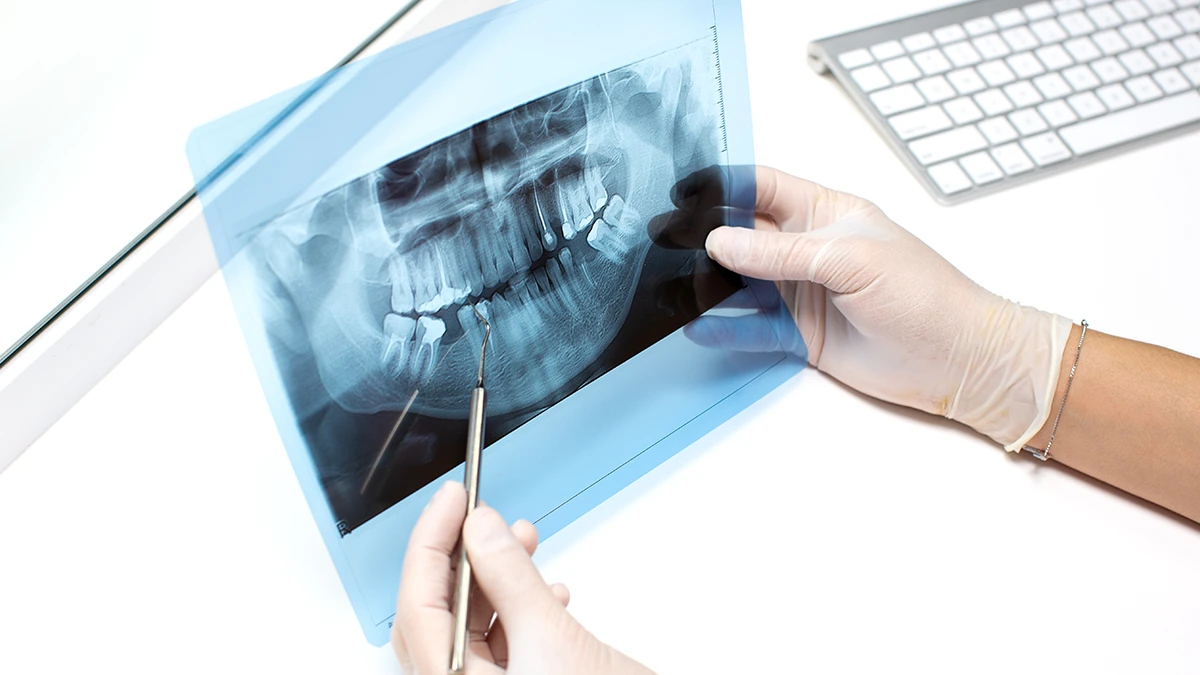

Biliyoruz ki, elinize bir 20’lik diş röntgeni geçtiğinde, o siyah, beyaz ve gri tonlardan oluşan görüntünün ne anlama geldiğini merak edebiliriz. Aslında, diş röntgeni nasıl okunur sorusunun cevabı, deneyimli bir göz için bir hikaye kitabını okumak gibidir. İşte hekimlerimizin bu görüntülerde dikkat ettiği kritik noktalar:

Röntgen görüntüsü, cerrahi bir operasyon öncesinde adeta yol haritamızdır. Tüm riskleri ve zorlukları önceden görmemizi sağlayarak, operasyonu daha güvenli ve öngörülebilir hale getiririz.

Çekim kararını verirken sadece ağrıyı değil, röntgenin sunduğu bilgileri de dikkate alırız. Bu görüntüler, tedavi planlamamızda belirleyici rol oynar: